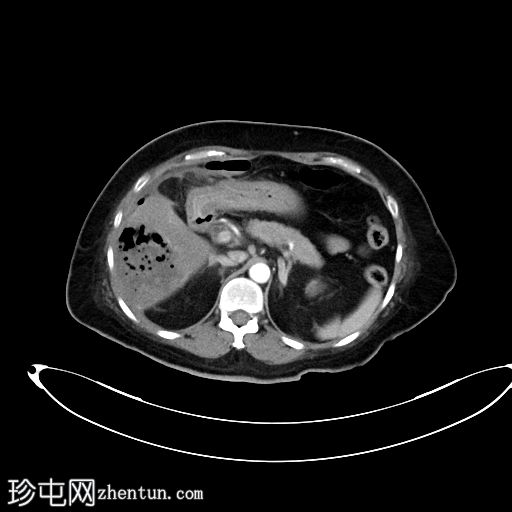

超声检查

2.png

肝胆系统

3.png

肝脏第6和第7段可见多个高回声气体腔,遮挡肝脏后部

肝脏其他部位形态及回声纹理正常

胆总管扩张,无结石,肝内胆管未见扩张

其他方面正常无游离液体